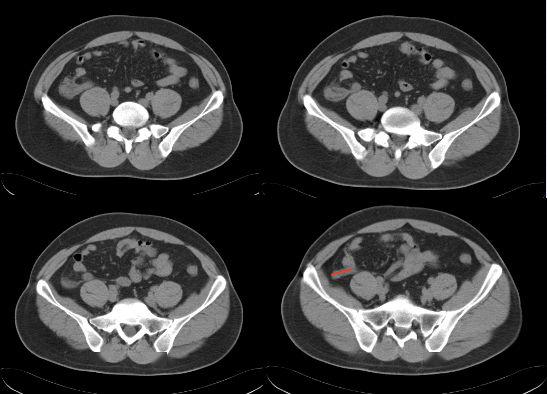

【腹腔镜篇】腹股沟疝手术

经脐单孔腹腔镜治疗小儿斜疝及鞘膜积液 - 好大夫在线